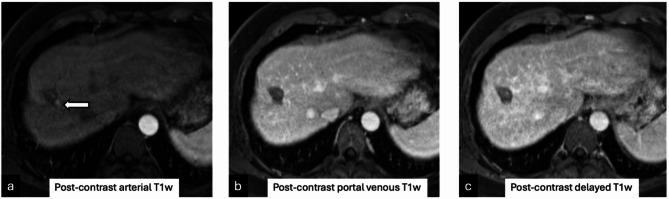

背景:通过肝移植前横断面成像准确评估肝细胞癌存活情况对于肝移植后正确的器官分配和患者的整体预后非常重要。目的:通过对比增强多期CT和MRI,确定LI-RADS TRA与外植体病理在热消融患者中的准确性。材料和方法:由三名委员会认证的放射科医生对2001年3月至2019年9月在一家三级医院接受热消融和肝移植治疗的119例连续成人HCC患者的影像学研究进行回顾性研究。将每个肿瘤的LI-RADS TRA分类与外植体病理进行比较。采用Cohens Kappa检验和Fleiss κ检验,95%置信区间采用bootstrap技术。结果:经皮热消融治疗的119例hcc患者(中位年龄59岁,男性95例[80%])中,68%完全坏死,32%病理存活。在外植体上存活的肿瘤在治疗前成像时较大(中位数为2.4 vs. 2.1 cm;P = 0.02),组间移植前消融腔大小无差异(分别为4.0和3.9 cm;p = 0.58)。LI-RADS TRA对存活肿瘤的NPV为71% (68-74);PPV为62.5% (39 ~ 81)(p = 0.01),敏感性为19%(9.4 ~ 32),特异性为95%(89 ~ 98),准确性为70%(63 ~ 77)。在外植体上,33例患者中发现55例意外治疗naïve移植前成像不可见的存活肿瘤。结论:即使应用于相对均匀的经皮消融队列,LI-RADS TRA的“不可存活”类别在预测肿瘤缺失方面也表现出较低的敏感性。与外植体病理相比,MRI在预测肿瘤生存能力方面比CT更准确。

Results: Of the 119 patients (median age 59 years, 95 [80%] male) with 165 HCCs treated with percutaneous thermal ablation, 68% were completely necrotic and 32% were viable on pathologic analysis. Tumors viable on explant were larger on pre-treatment imaging (median 2.4 vs. 2.1 cm; p = 0.02) with no difference in pre-transplant ablation cavity sizes between groups (4.0 vs. 3.9 cm, respectively; p = 0.58). NPV of LI-RADS TRA for viable tumor was 71% (68-74); PPV of 62.5% (39-81) (p = 0.01) with a sensitivity of 19% (9.4-32), specificity of 95% (89-98), and accuracy of 70% (63-77). On explant, 55 incidental treatment naïve viable tumors, not visible on pre-transplant imaging, were found in 33 patients.

Conclusion: The "non-viable" category of LI-RADS TRA even when applied to a relatively uniform percutaneous ablation cohort, demonstrated low sensitivity in predicting absence of viable tumor. MRI had more accuracy than CT in predicting tumor viability when compared to explant pathology.